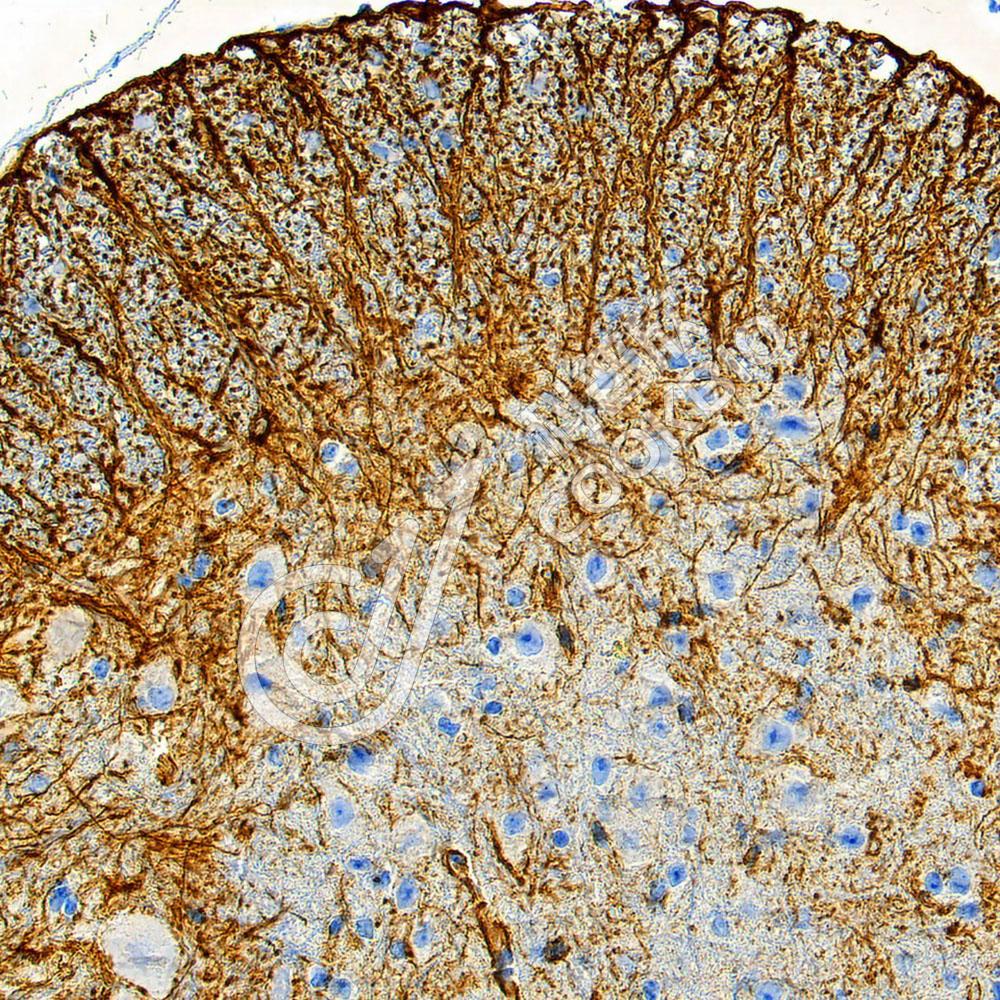

IHC检测GFAP蛋白(货号 K545300).

样品: 小鼠脊髓, 4%多聚甲醛 (货号KSG1101) 固定12-24小时.

抗原修复: Tris-EDTA抗原修复液(pH 9.0) (KSG1203), 98℃, 20分钟.

—抗: 1: 1300稀释, 4℃ 孵育过夜.

二抗: S-vision免疫组化多聚二抗(山羊抗兔),即用型 (货号KB3906), 室温孵育20分钟.

样品: 大鼠脊髓, 4%多聚甲醛 (货号KSG1101) 固定12-24小时.